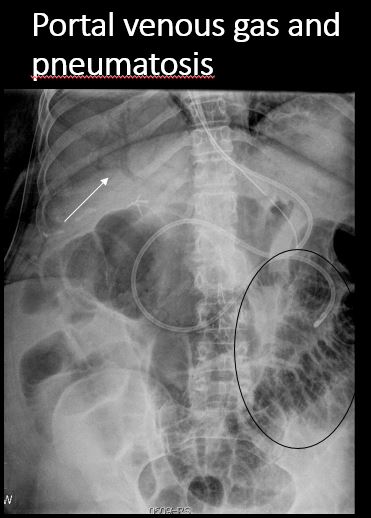

There is air in the wall of the small or large bowel. [Yes/No]

There is portal venous or other intravascular gas. [Yes/No]